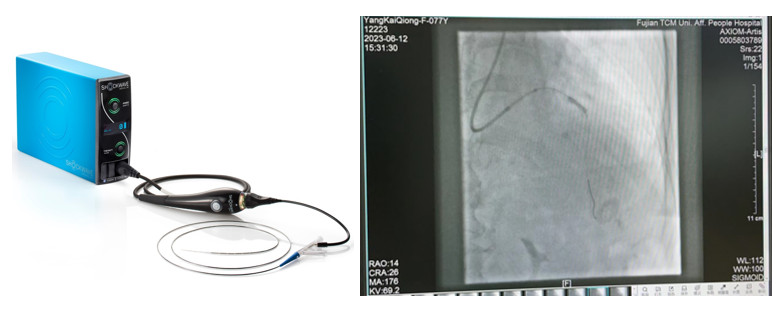

冠脈內(nèi)沖擊波治療術(shù)